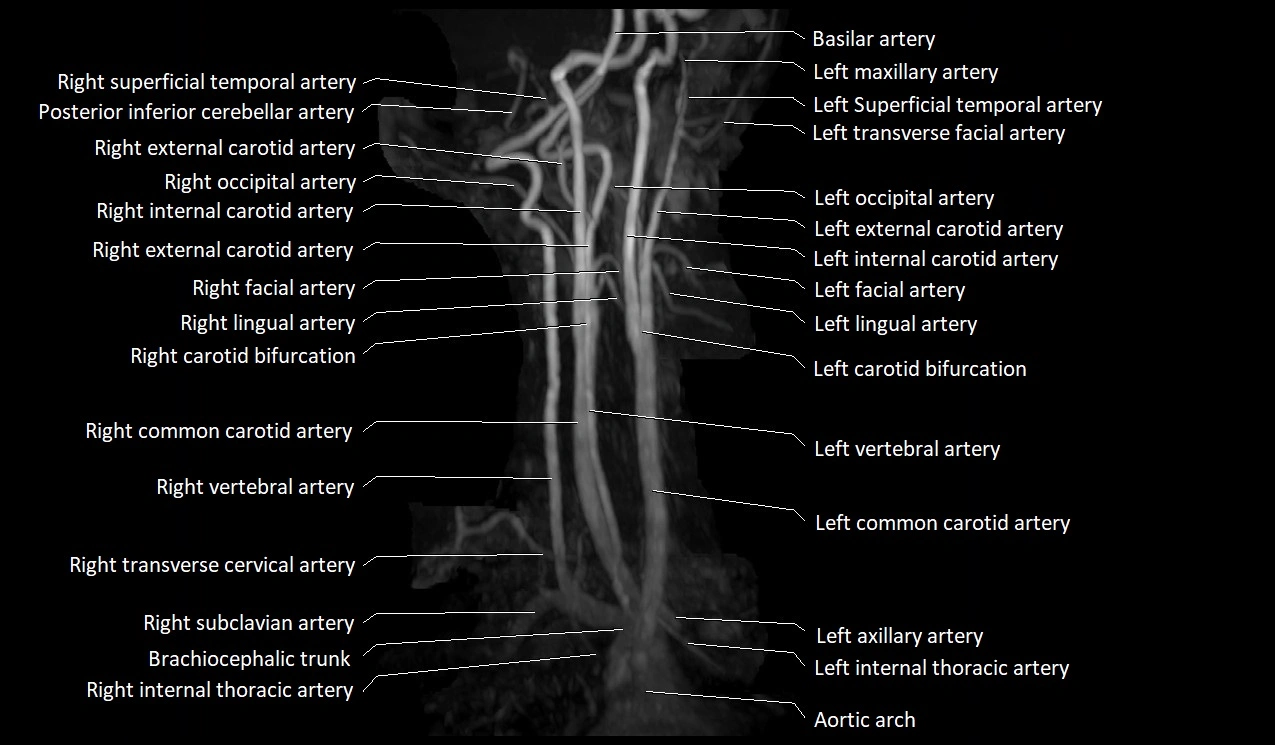

MRI images

image